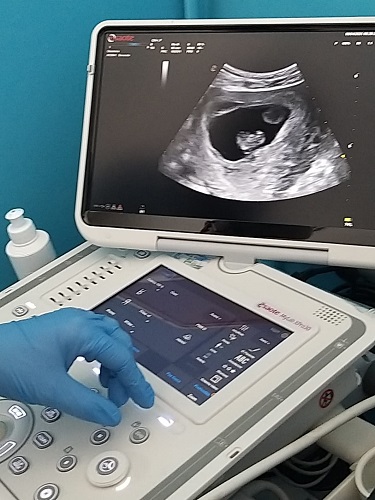

MODENA – Due nuovi ecografi per rafforzare l’assistenza sanitaria in Appennino modenese. I dispositivi sono in funzione da qualche settimana presso le Case della Salute di Pievepelago e Fanano, per rafforzare la presa in carico dei pazienti, soprattutto donne in gravidanza. In entrambe le strutture gli ecografi saranno a disposizione del Consultorio ginecologico-ostetrico per ecografie di supporto: dalla datazione nella gravidanza iniziale, alla rilevazione del battito cardiaco fetale laddove altrimenti difficoltosa, al controllo del posizionamento intrauterino del feto e della sede placentare fino al corretto posizionamento di un dispositivo intrauterino e il controllo dello spessore endometriale in caso di sanguinamenti uterini anomali o la presenza di una massa pelvica. Nella Casa della Salute di Fanano l’ecografo sarà anche a disposizione del Servizio di Radiologia che renderà disponibili alcune prestazioni ecografiche in concomitanza delle sedute di radiologia tradizionale. Sempre nella struttura di Fanano, stante il numero non elevato di prenotazioni, si è deciso di dar vita a un progetto sperimentale per ottimizzare l’uso del dispositivo, che coinvolge direttamente nella prescrizione i Medici di Medicina Generale (MMG) del solo sub-ambito di Fanano-Sestola-Montecreto.